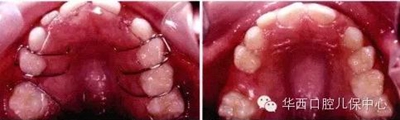

圖示:乳尖牙至乳磨牙的寬度大于繼承恒牙的寬度

剩余的間隙稱為替牙間隙(leeway space)